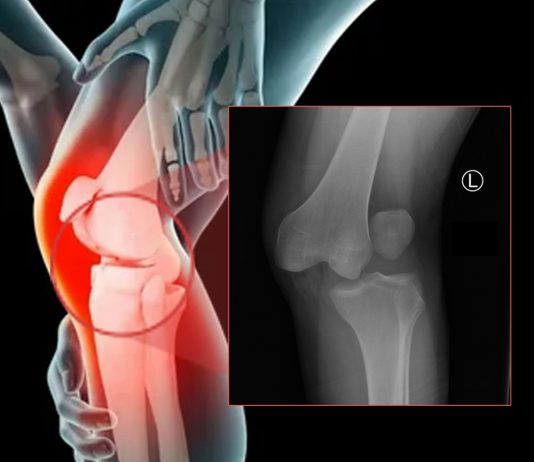

Diz Eklemi Çıkıklarına Genel Yaklaşım